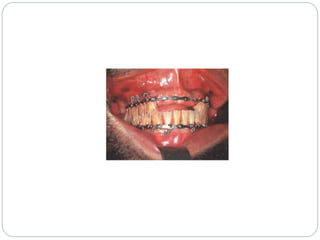

‫دندانی‬ ‫بستن‬ ‫سیم‬:

‫بار‬ ‫آرچ‬

‫آ‬‫لوووپ‬ ‫وی‬ ‫ی‬

‫پیوسته‬ ‫سیم‬

‫گویند‬ ‫می‬ ‫بسته‬ ‫روش‬ ‫را‬ ‫سیم‬ ‫بستن‬ ‫روش‬ ‫با‬ ‫شکستگی‬ ‫درمان‬

‫شود‬ ‫می‬ ‫بسته‬ ‫آرچ‬ ‫یا‬ ‫سیم‬ ‫فک‬ ‫دو‬ ‫هر‬ ‫برای‬

‫ش‬ ‫می‬ ‫بسته‬ ‫پایین‬ ‫به‬ ‫باال‬ ‫فک‬ ‫کامل‬ ‫حرکتی‬ ‫بی‬ ‫رعایت‬ ‫برای‬‫ود‬

IMF‫و‬MMF:Inter Maxillary Fixation

‫حداقل‬6‫هفته‬IMF‫است‬ ‫الزم‬